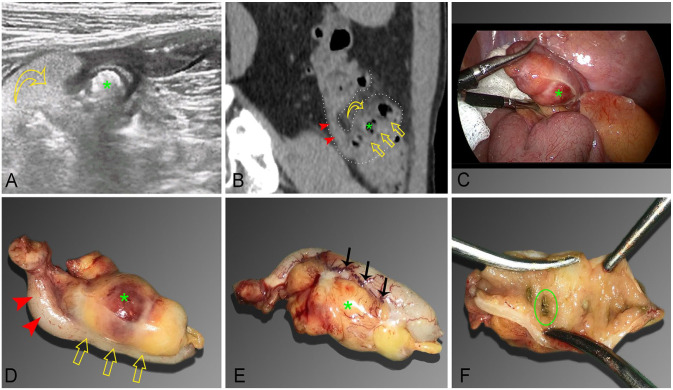

Appendiceal diverticulitis is an uncommon condition that clinically resembles acute appendicitis. However, it is an incidental finding in histopathological studies and is rarely diagnosed preoperatively by imaging studies. In this article, we present the clinical and imaging findings of a male patient presenting with right upper quadrant pain with a preoperative imaging diagnosis of appendiceal diverticulitis. He underwent laparoscopic appendectomy and confirmed the diagnosis of appendiceal diverticulitis. This is a rare preoperative diagnosis. The management is often like typical appendicitis which is appendectomy. It is important to differentiate it from diverticulitis of the small intestine or colon because these diseases usually require only conservative treatment.